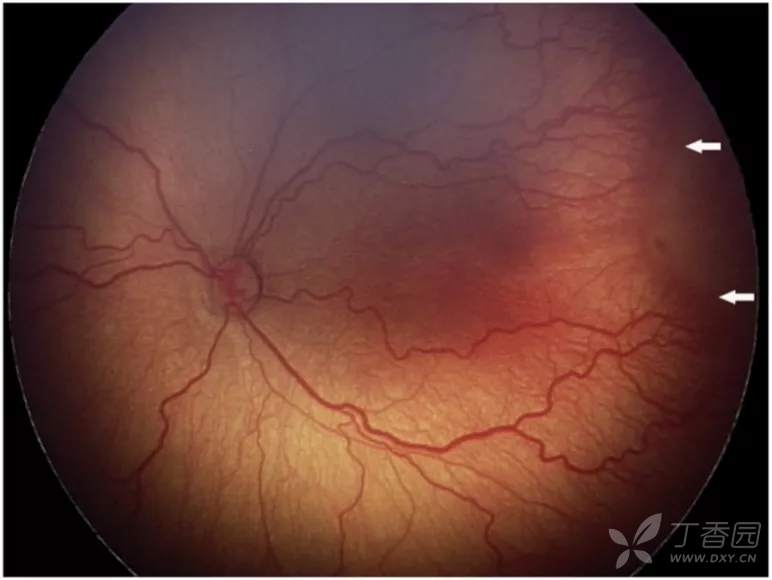

02、plus病变和plus病变前期

plus病变指视网膜血管扩张和迂曲。plus病变前期定义为视网膜血管异常扩张和迂曲,但不足以诊断为plus病变。

图. plus病变,明显静脉扩张和动脉纡曲。plus病变与外周眼底表现不成比例,扁平的新生血管形成(3期,白色箭头)。